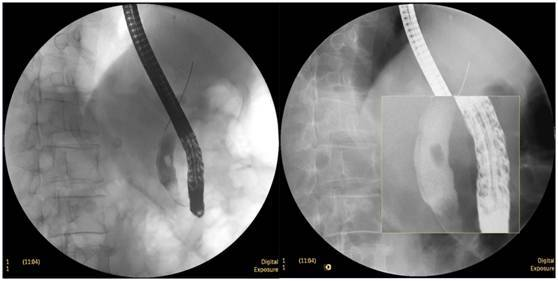

食管惡性腫瘤

食管癌并狹窄內(nèi)鏡下擴(kuò)張支架植入術(shù),支架在脊柱背景下依然能清晰顯示。